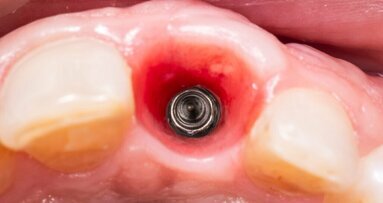

罗斯托克大学医学中心的牙医对这项新技术进行了人工牙齿试验,并取得了积极的结果。

带有集成压电陶瓷层叠致动器的牙科锉刀。 (图片:Fraunhofer IKTS)